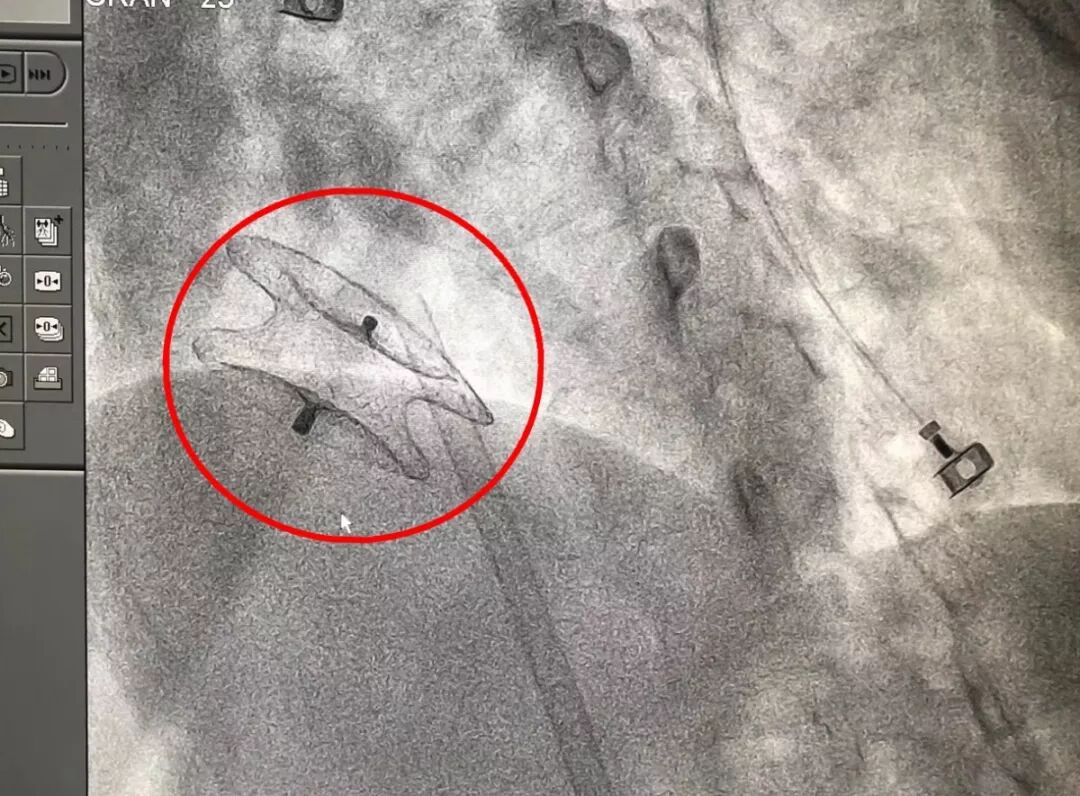

考虑到李阿姨的病情非常紧急,医生决定为李阿姨进行手术。第二天,李阿姨被送进了导管室,医生通过穿刺李阿姨的股静脉,将双盘状封堵器送至左心房。打开左房面,通过特制鞘管,在X线和超声的引导下,将大小合适的封堵器送至病变部位封堵缺损。术中通过透视后前位,两盘片基本呈同心圆状。